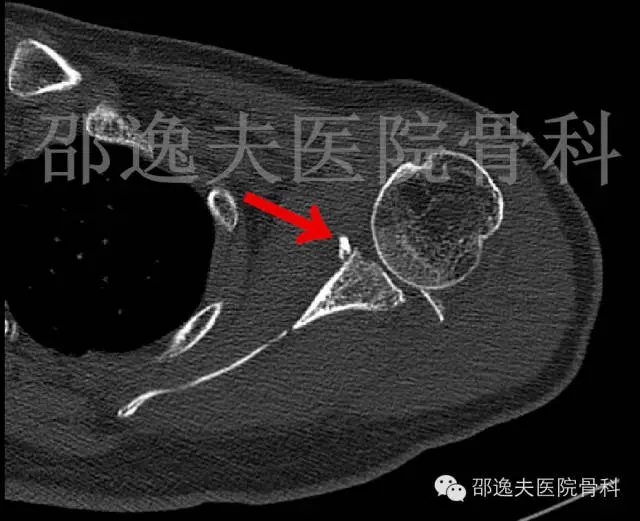

肩部CT扫描

这是典型的骨性Bankart损伤,即指外伤导致肩关节前脱位后与肩关节盂前下缘撞击发生的关节盂前缘撕脱骨折。